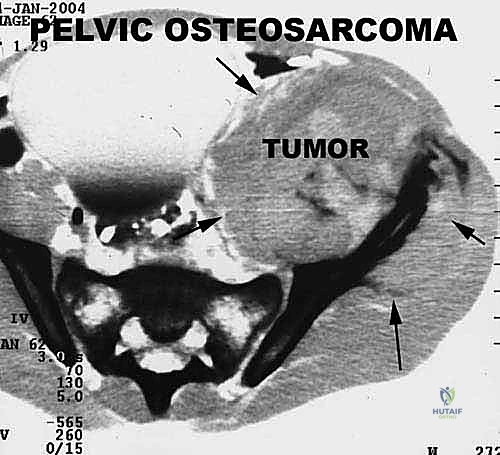

* ساركوما إيوينغ (Ewing Sarcoma): تصيب غالباً العظام الطويلة والحوض.

تحديد مراحل الورم (Staging): نظام Enneking

تحديد مرحلة الورم هو الخطوة الأهم قبل أي تدخل جراحي. يعتمد الدكتور هطيف على نظام (Enneking) لتحديد مراحل أورام العظام، والذي يعتمد على ثلاثة عوامل:

1. درجة الورم (Grade - G): بناءً على الفحص النسيجي (G1 منخفض الدرجة، G2 عالي الدرجة).

2. الموقع (Site - T): هل الورم داخل الحيز العظمي (Intracompartmental - T1) أم اخترق القشرة وخرج للحيز الخارجي (Extracompartmental - T2)؟

3. الانتشار (Metastasis - M): هل انتقل الورم لأعضاء أخرى (M0 لا يوجد، M1 يوجد انتشار)؟

بناءً على هذا التقييم الدقيق، يتم وضع خطة جراحية متكاملة لضمان استئصال الورم بالكامل دون ترك أي خلايا سرطانية.